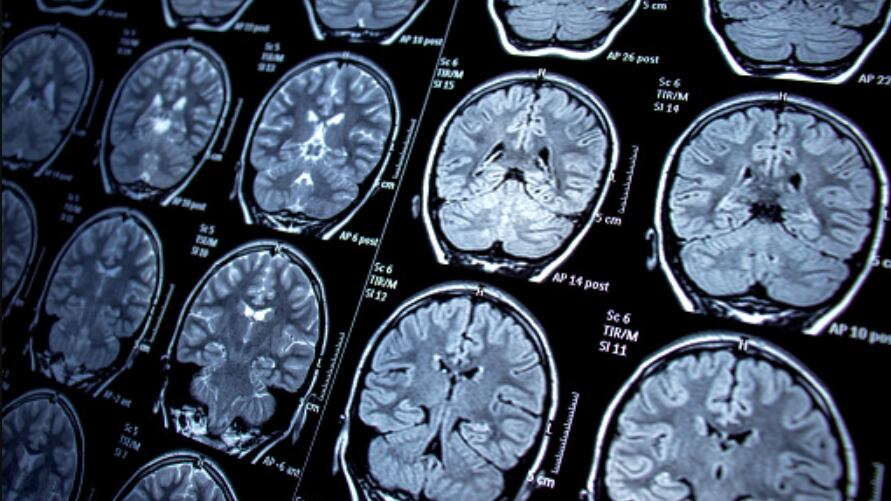

No entanto, embora inicialmente nenhum problema tenha sido identificado, quando realizada uma varredura na região do cérebro, os exames confirmaram uma alteração e um glioma pontino difuso, que é um tumor que fica localizado em uma região do tronco encefálico.

Segundo os informes médicos, o tumor foi localizado junto com uma forma leve de hidrocefalia, em que há excesso de líquido acumulado no cérebro.